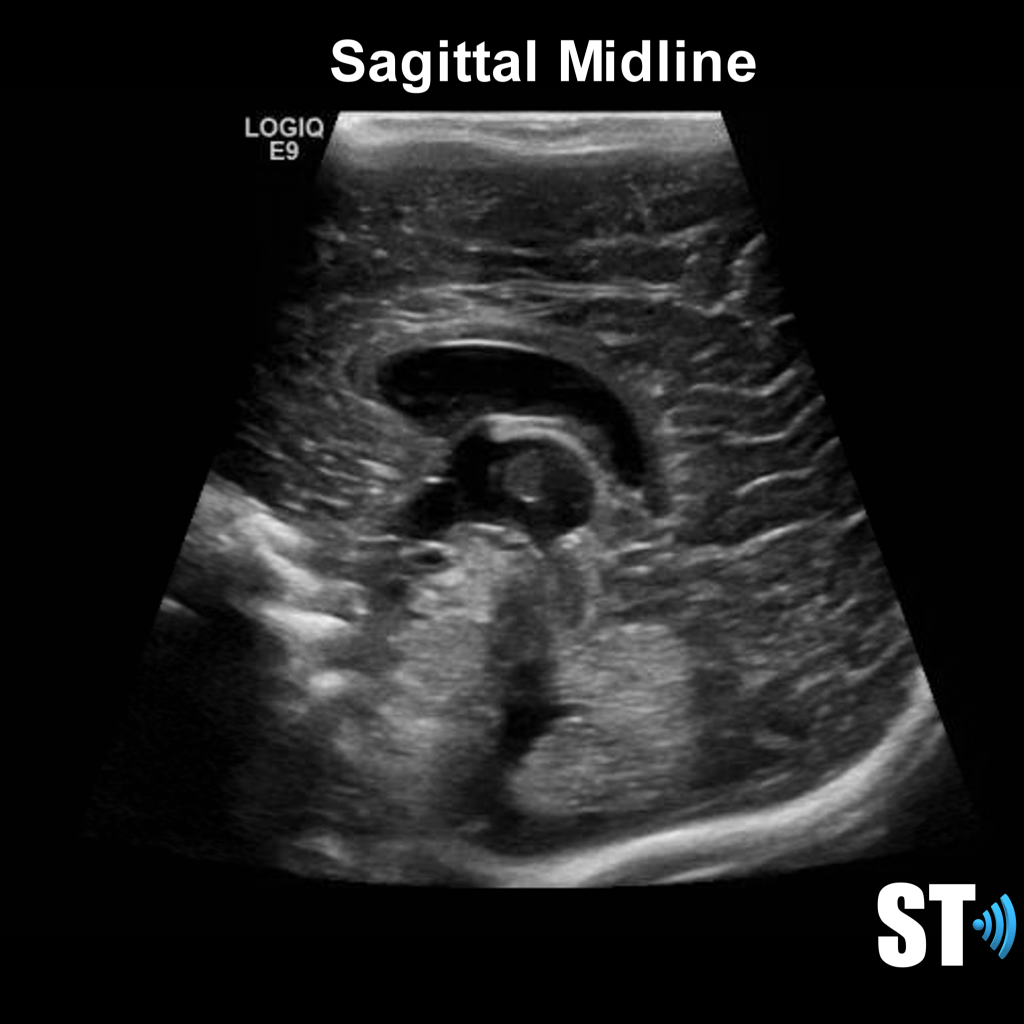

We use primarily the anterior fontanelle using a coronal, sagittal and parasagittal views. Also we scan through the mastoid fontanelle (for the posterior fossa and cerebellar views) and posterior fontanelle (for posterior structures especially the occipital horn to detect dependent hemorrhage) and temporal views for further evaluation.

Sagittal Anterior Fontanelle Views